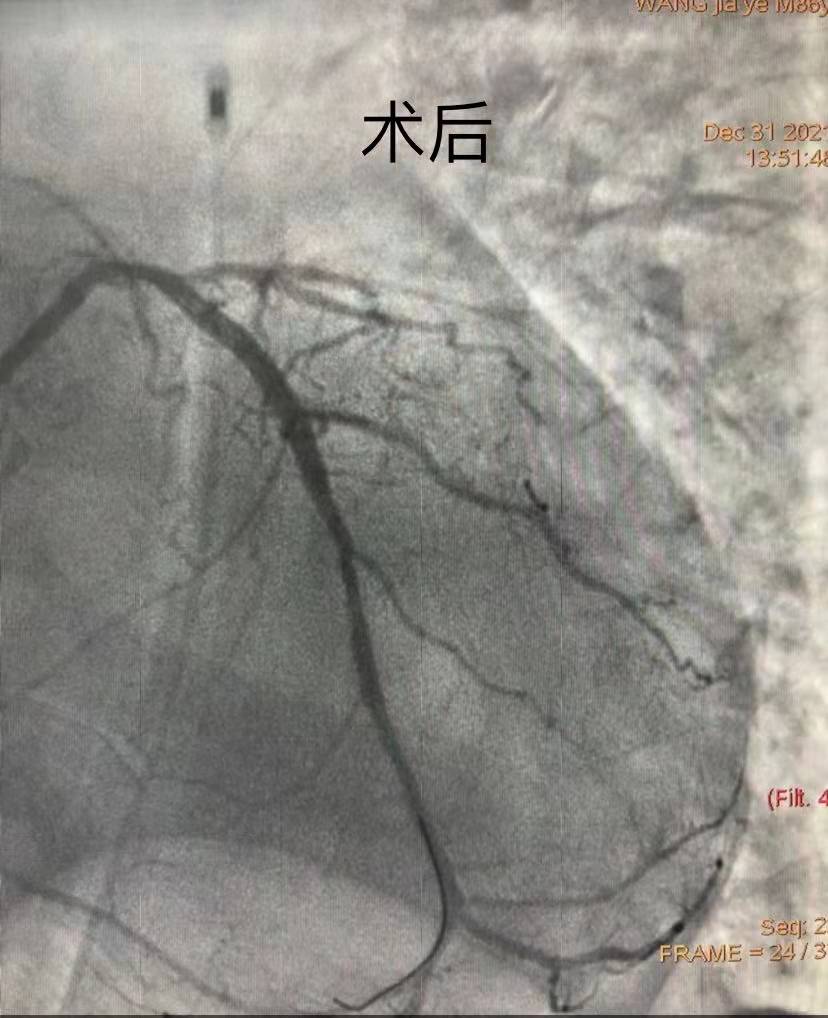

團(tuán)隊(duì)綜合考慮后判斷,LCX是此次心肌梗死的“元兇”。開通病變部位的機(jī)會(huì)只有一次,必須做到“快、準(zhǔn)、狠”。汪院長(zhǎng)團(tuán)隊(duì)經(jīng)驗(yàn)豐富,技術(shù)嫻熟,導(dǎo)絲小心通過,球囊充分?jǐn)U張,最后在病變部位植入支架,所有操作一氣呵成。復(fù)查造影顯示,病變部位狹窄小于10%,手術(shù)獲得成功。